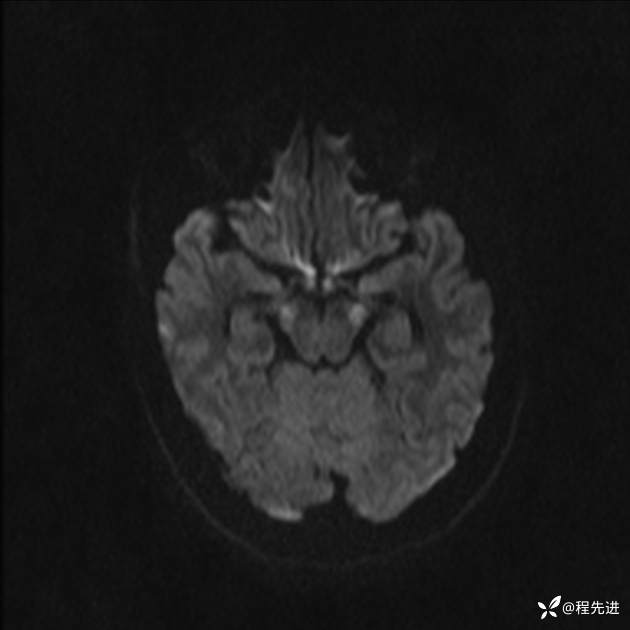

【患者信息】:女,25岁

【现病史及既往史】:言语含糊、意识状态改变1天。有下段剖宫产术10天病史。

【检查】